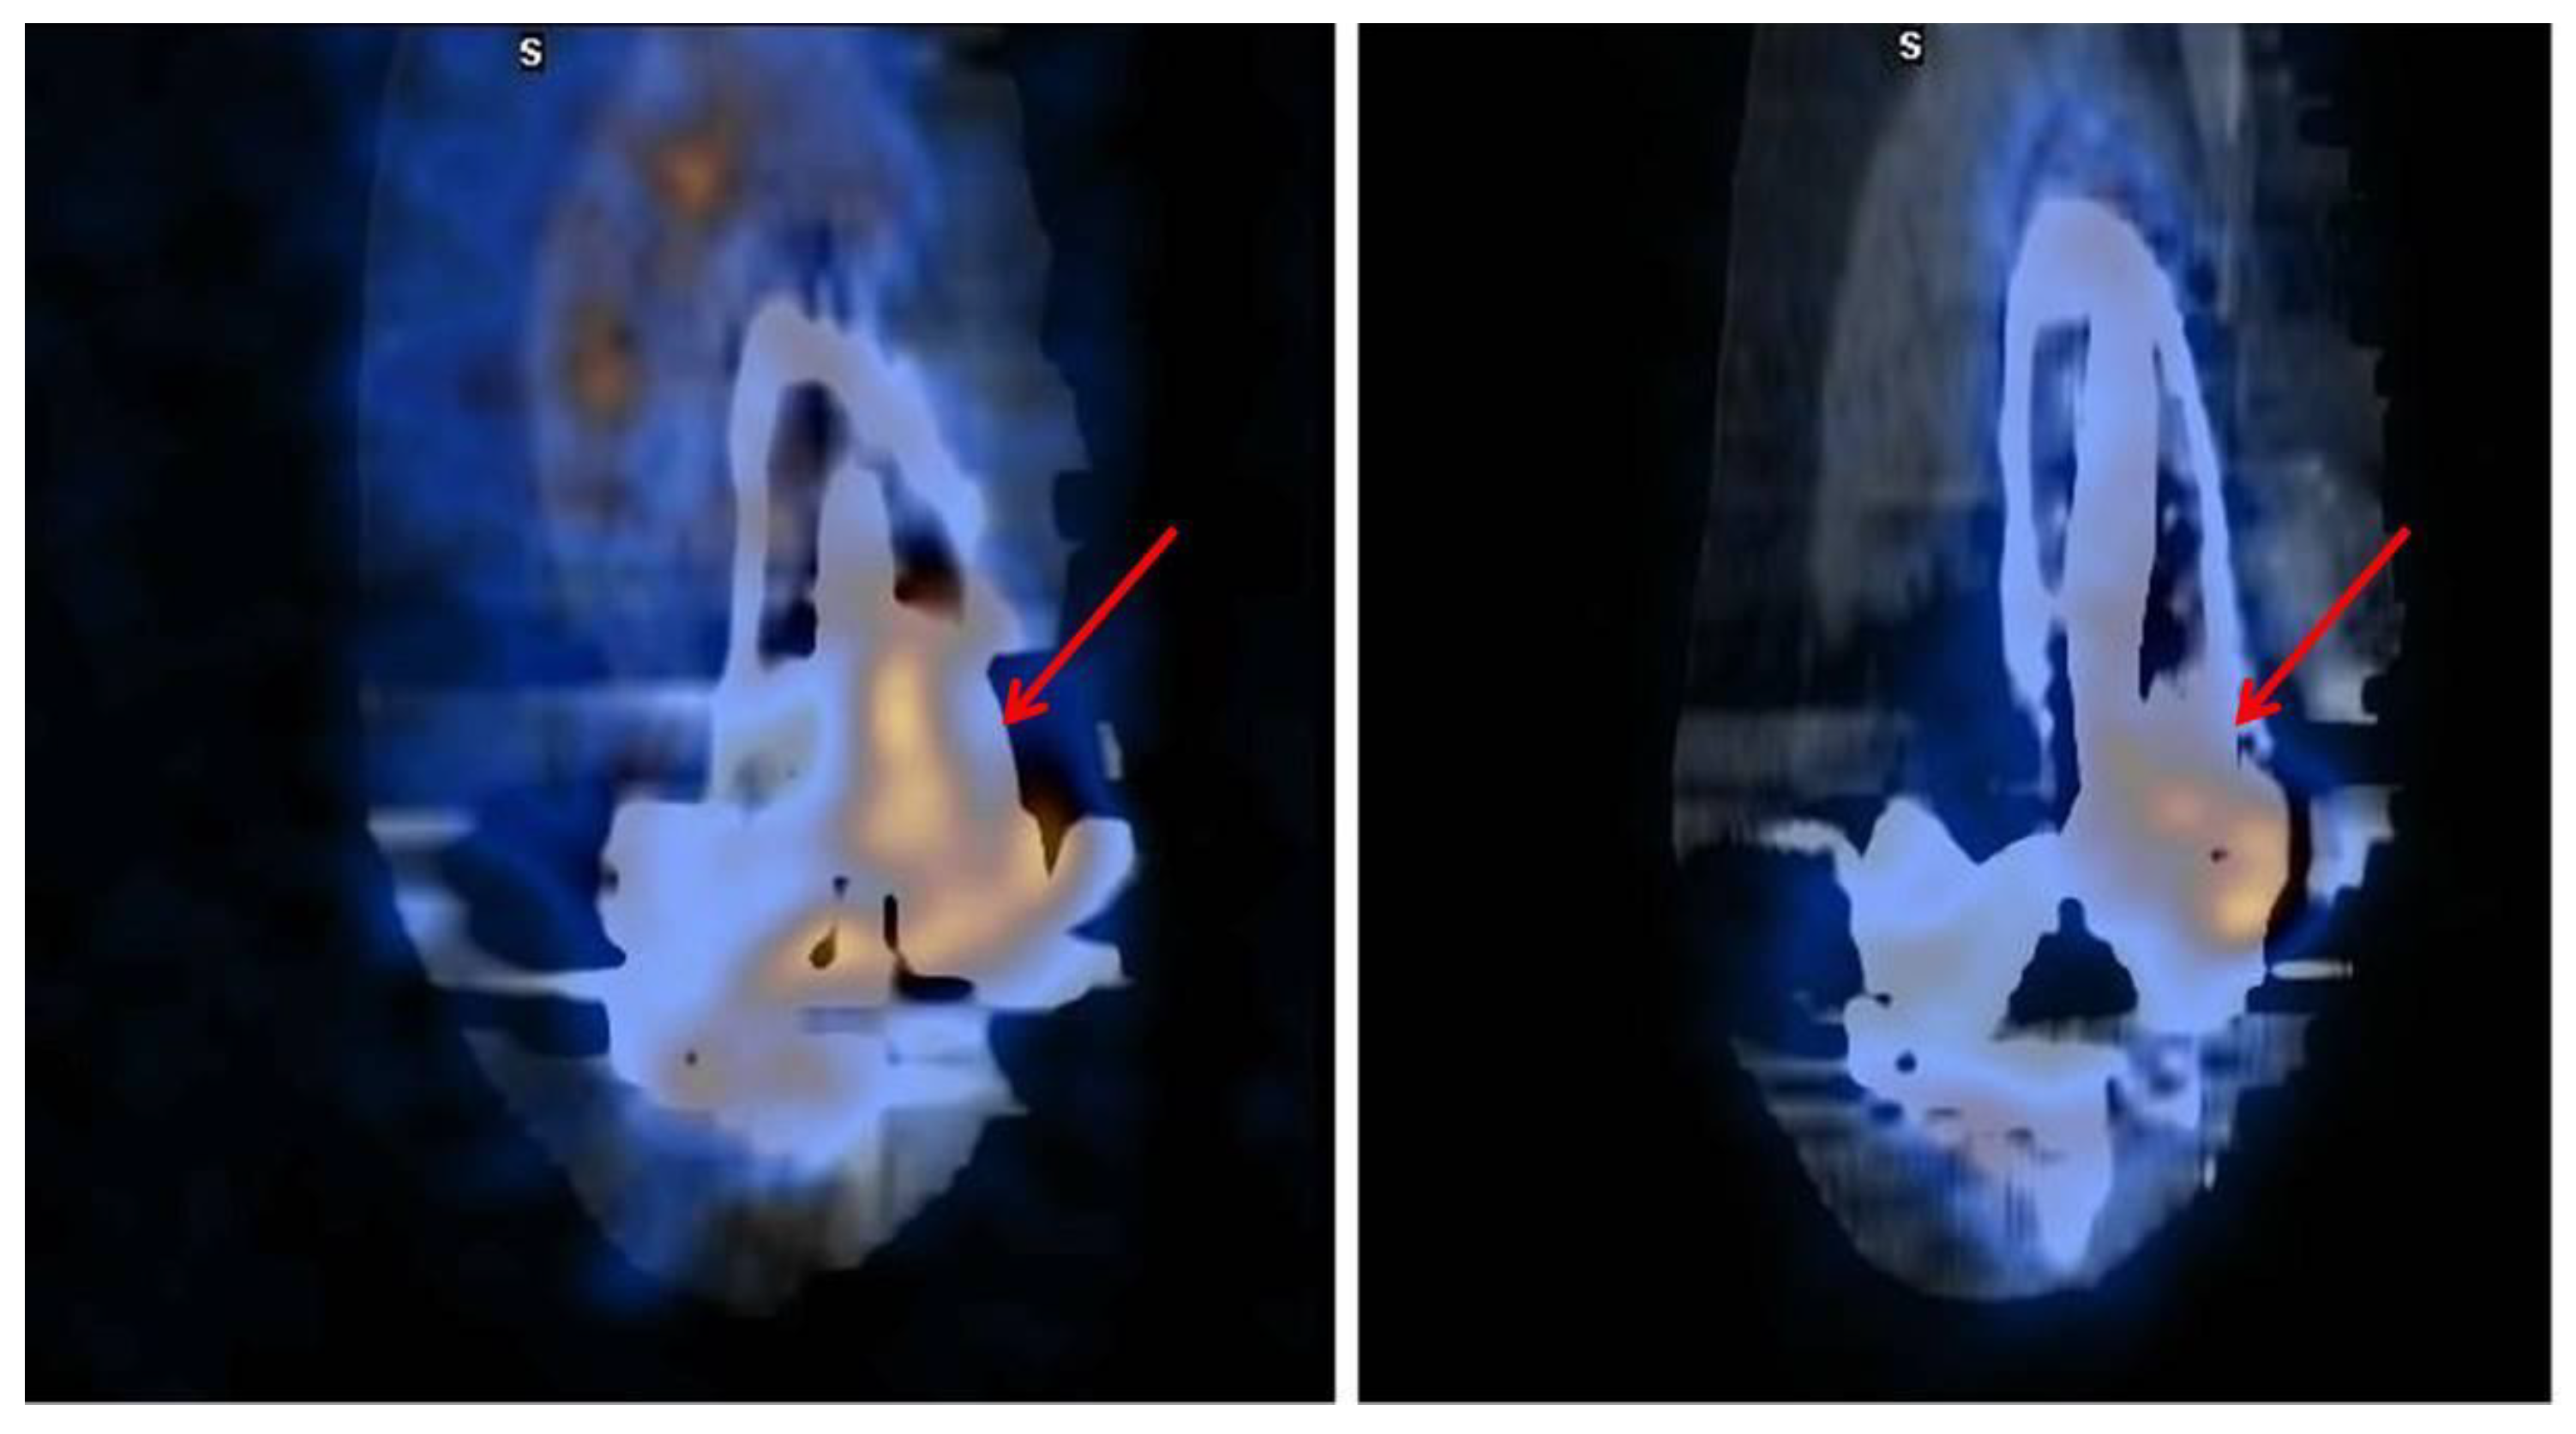

3.1. SPECT/CT plus 99mTc, 67Ga or Labeled Leucocyte Scintigraphy

5. Monitoring Musculoskeletal Infections: The Role of NM

- Domínguez, M.L.; Lorente, R.; Rayo, J.I.; Serrano, J.; Sánchez, R.; Infante, J.R.; García, L.; Durán, C. SPECT-CT with 67Ga-citrate in the management of spondylodiscitis. Rev. Esp. Med. Nucl. Imagen Mol. 2012, 31, 34–39. [Google Scholar] [CrossRef] [PubMed]

- Tamm, A.S.; Abele, J.T. Bone and Gallium Single-Photon Emission Computed Tomography-Computed Tomography is Equivalent to Magnetic Resonance Imaging in the Diagnosis of Infectious Spondylodiscitis: A Retrospective Study. Can. Assoc. Radiol. J. 2017, 68, 41–46. [Google Scholar] [CrossRef]

- Righi, E.; Carnelutti, A.; Muser, D.; Di Gregorio, F.; Cadeo, B.; Melchioretto, G.; Merelli, M.; Alavi, A.; Bassetti, M. Incremental value of FDG-PET/CT to monitor treatment response in infectious spondylodiscitis. Skeletal Radiol. 2020, 49, 903–912. [Google Scholar] [CrossRef]